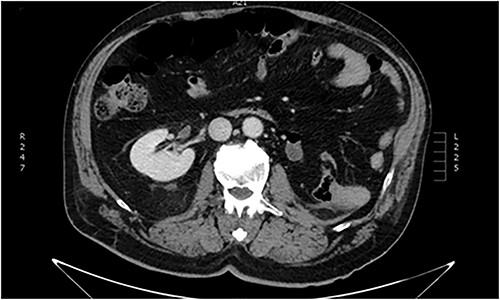

Imaging investigation with thoracic x-ray revealed 9th to 11th posterior rib fractures, as well as small pneumothorax on the right rib cage. Abdominal ultrasound revealed no internal bleeding or fluid within the peritoneal cavity and spaces, but an injured ectopic left kidney was detected within the pelvic cavity, previously unbeknownst to the patient. Further imaging with abdominal and pelvic computed tomography (CT) scan confirmed the occurrence of a grade III laceration (according to the American Association of the Surgery of Trauma—AAST renal injury grading scale) of the ectopic kidney (Figs. 1 and 2).

Abdominal CT imaging. Absence of left kidney from its usual anatomic position.